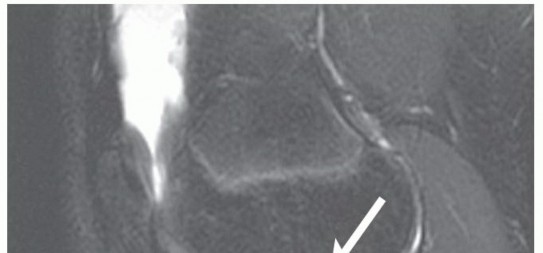

The “shift” that occurs with the ACL-deficient knee at the time of injury causes an impaction injury on the posterior aspect of the tibial plateau against the distal femur at the sulcus terminalis as the tibia translates anteriorly on the femur. Characteristic bone bruises in this location on magnetic resonance imaging (MRI) are pathognomonic for ACL injury (

FIG 2

).

• Sagittal MRI through the lateral aspect of the knee demonstrating characteristic bone bruise pattern for an acute ACL injury (thin arrow). Note increased signal on the posterior aspect of the lateral tibial plateau and the distal aspect of the femur at the sulcus terminalis (thick arrow).